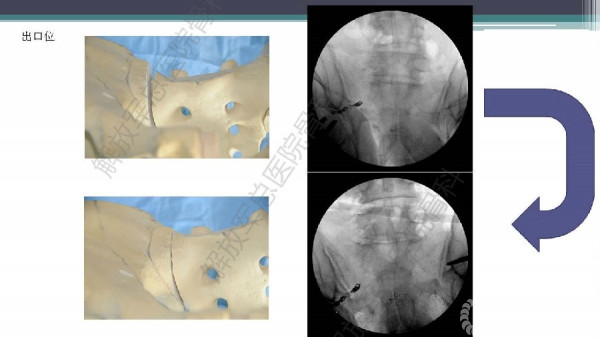

随着建筑和交通运输业的快速发展,合并骨盆、髋臼骨折多发伤、复合伤患者逐年增加,病死率和致残率都非常高。由于多发伤及复合伤、休克等往往不能在急性期对骨盆骨折进行确切复位及内固定,导致陈旧性骨盆骨折畸形愈合,从而产生一系列严重并发症,并且畸形矫正手术难度大、风险高、效果差。因此在抢救复苏后能不能尽早地、小切口甚至不切开、精确复位与固定骨盆骨折,防止陈旧性骨盆畸形愈合形成,成为广大骨科医生的挑战。解放军总医院创伤骨科在骨盆、髋臼骨折微创治疗方面做了一些工作,从微创理论探讨、到手术方法的改进,乃至钢板螺钉、微创复位器械等相继研发,形成了一系列的解决方案和配套内固定产品,为骨盆髋臼骨折的微创治疗奠定了基础。本幻灯则通过一例陈旧骨盆骨折畸形愈合的复杂治疗做引,通过介绍骨盆空间移位方式、透视特点、骨盆随意外架复位系统、复位原理以及1例典型病例的具体实施方案来综合、全面介绍我院微创骨盆髋臼骨折复位、固定新技术。